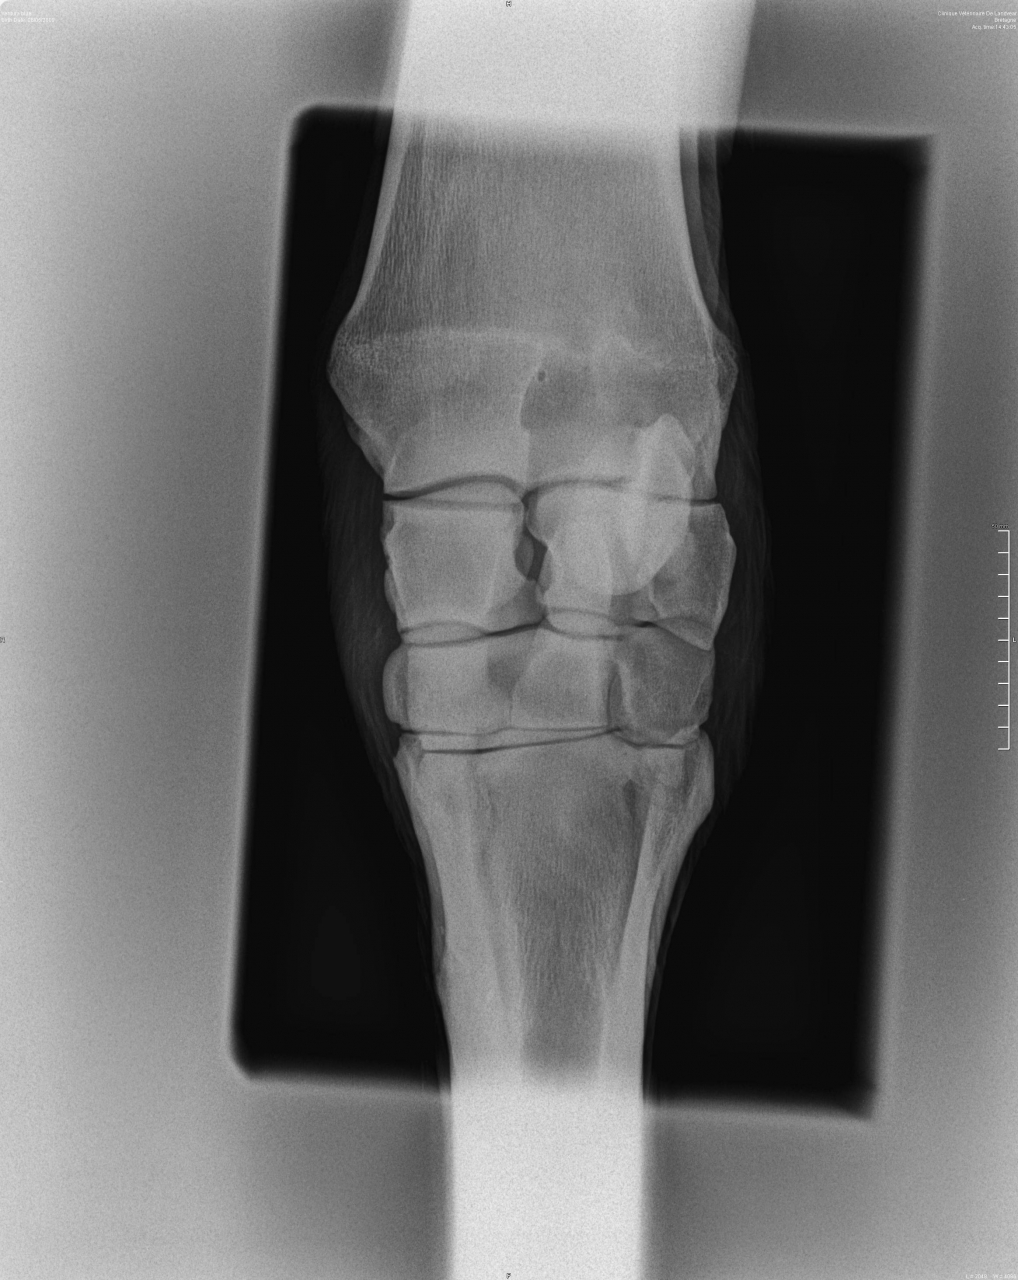

| Dire merci | Bonsoir, Pour poser un peu le problème, ma jument a depuis un bon mois un soucis au genou, surement dû à un coup. Au début c'était engorgé puis ça a vite dégonflé avec application d'argile. Petite boiterie mais rien de bien méchant. Le veto l'avait vu et conseillé d'appliquer de l'ekyflogil. Par la suite j'ai fais des emplâtres d'argile, plutôt efficace. Toujours un mini mini boiterie. On a été à la mer marcher dans l'eau etc... Sur le genou il y a une bosse dure, non mobile, non douloureuse (je peux tripoter la bosse, lui plier le membre sans soucis). Bref, voyant que la masse est toujours là je décide de faire des radios/echo redoutant le suros. Je l'envoie en clinique, le veto touche et me dit d’emblée que c'est surement un suros... il fait les clichés, un de face et un de profil. Je vais avec lui voir les résultats, bon non finalement ce n'est pas un suros. On fait ensuite une echo où on ne voit pas grand chose. Pas simple de dire ce que c'est exactement, le veto évoque un nodule fibreux indépendant du tendon extenseur. Alors le protocole qu'il m'indique de suivre est, ekyflogyl pendant encore une semaine 2x par jour. Si le nodule évolue et/ou est toujours gênant il faudra pratiquer une ablation. Je sais qu'il y a des vetos sur le forum, au vu des radios j'aimerais avoir des avis, sur cette chose j'attend pas de miracles, juste si quelqu'un peut m'en dire plus... vaut mieux opérer direct ? merci d'avance. celle de profil avec la masse entourée en rouge ![]() et celle de face, ou on ne voit pas grand chose ![]() |